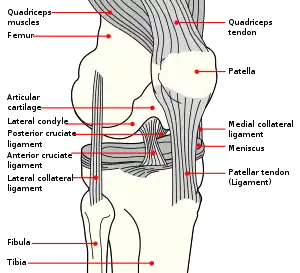

Skeletal components involved in the unhappy triad include: patella, femur, tibia. No muscles are directly involved in this injury, only ligaments; However, strengthening the hip flexor and hip extensor muscles may help alleviate the injury.

The medial collateral ligament, posterior cruciate ligament, anterior cruciate ligament, and lateral collateral ligament are the four primary ligaments of the knee. The medial and lateral collateral ligaments primarily provide support to varus and valgus forces whereas the anterior and posterior cruciate ligaments prevent anterior and posterior translation of the tibia on the femur.[2]

The anterior cruciate ligament is one of the four crucial ligaments in the knee. It originates from the lateral condyle of the femur and goes to the intercondyloid eminence of the tibia. Its function is to provide stability in the knee and minimize stress across the knee joint. It also restrains excessive forward movement in the leg and limits rotational movements in the knee.

Meniscus

The medial meniscus is a C-wedge shaped piece of cartilage that acts as a"shock absorber" between the femur and the tibia. Each knee has two menisci, one at the outer edge and one at the inner edge of the knee. The menisci are tough and rubber-like to help cushion the joint and help keep it stable.

The lateral meniscus is also known as the external semilunar fibrocartilage. It is a fibrocartilage band on the lateral side of the knee joint and can easily be injured with torsional stress or direct force.